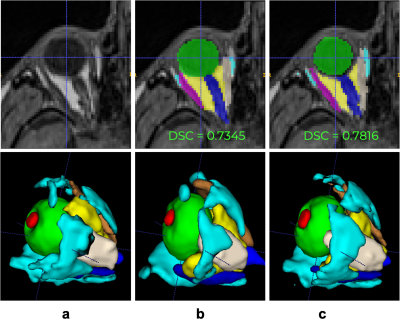

Figure 2 (a-bottom) Manual annotation on 9 ROI: lens (red), globe (green), optic nerve (dark blue), intraconal fat (yellow), extraconal fat (cyan), lateral rectus muscle (pink), medial rectus muscle (ivory), inferior rectus muscle (purple), and superior rectus muscle (orange). Examples of inference from (b top-bottom) Atlas-based and (c top-bottom) deep learning methods.

Atlas-based segmentation robustly extracted the 9 ROIs on new data. Figure 2b presents visual label results. Figure 3a presents similarity metrics on the manually annotated dataset (N=30 remaining labeled subjects). Median DSC values for lens and globe are 0.73, 0.74 respectively, while we establish new median DSC benchmarks for optic-nerve (0.91), muscles (0.58 to 0.76) and fat (0.67 and 0.75). DL-based segmentation showcased potential to replace atlas-based segmentation. Figure 2c reports visual label results. Figure 3b reports DL accuracy on 4 subjects as compared to manual annotations and in comparison with atlas-based performance. Despite the small sample size, DL has better performance for fat and muscles. Figure 4 presents DSC on (N =1210) of method A versus B. The DSC shows both segmentations are highly similar (DSC=0.9) for the optic nerve while much more variability is present for all other ocular structures (median DSC between 0.55 and 0.76). Axial-length agreement with ground-truth. Figure 5 shows the estimated axial length (Method A/Method B; mean 24.1 土 1/ 22.6 土 1.0 ). Agreement with reported average axial length measured from MRI (24.1 土 1.2 20) was higher for atlas based segmentation.